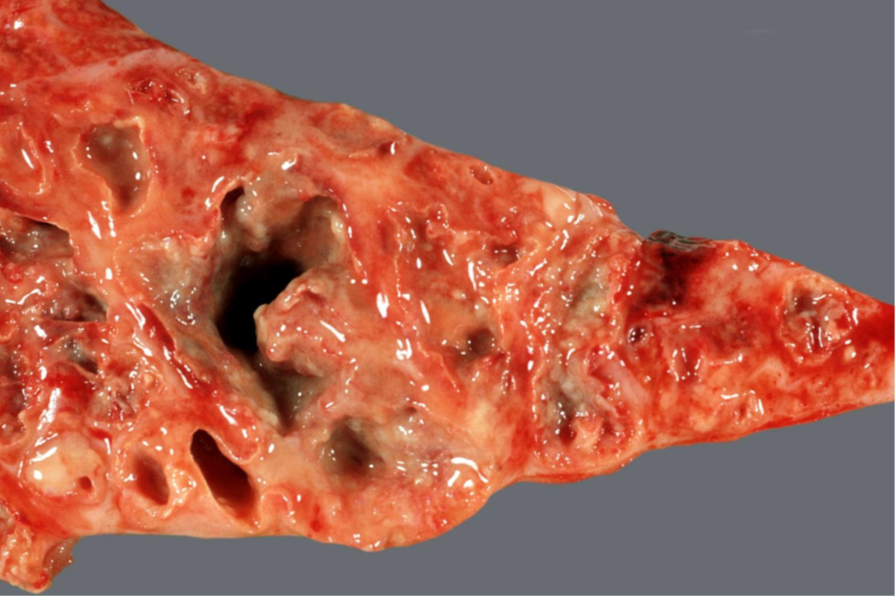

Rind, Niere: Hochgradige, chronisch-aktive, diffuse, eitrige Pyelonephritis mit Konkrementbildung, Papillennekrosen und sekundären Nierenrinden-Infarkten

Beschreibung:

auf der Organoberfläche lassen sich multiple, konfluierende weiße Herde, teilweise mit rötlichem (hyperämischem) Randsaum darstellen

im Anschnitt stellen sich die Herde als von Cortex bis in das Mark ziehende (radiäre), weiße bis rötliche Streifungen mit assoziierten Einziehungen der Oberfläche dar

Im dilatierten Nierenbecken befinden sich weiß-gelbe, grobbis feinkörnige Exsudatmassen/Konkremente

Hintergrundwissen/ Infektionsweg/ Pathogenese

Entzündung von Nierenbecken (Pyelitis) und Nierenparenchym (Nephritis)

im akuten Stadium hauptsächlich entzündliche und nekrotische Läsionen im Nierenbecken und Papillen

im chronischen Stadium dominiert die Bildung von Granulationsgewebe und Narbenbildung bis in das periphere Parenchym (pyelonephritische

Schrumpfniere) sowie chronische Niereninfarkte, im Nierenbecken befinden sich oft Fibrin, Zelldetritus und Konkremente

Infektionswege/Pathogenese:

aszendierend urogen ausgehend von Infektionen der Ureteren bzw. Harnblase (refluxiv) oder bei Urolithiasis (obstruktiv)

deszendierend hämatogen im Rahmen einer embolisch-eitrigen Nephritis (Ausscheidungsnephritis)

häufig Schwein (akute Pyelonephritis, v.a. weibliche Tiere direkt postpartal) und Rind (chronische Pyelonephritis, sporadisch puerperal) betroffen

Prädisponierend sind Faktoren, die eine Bildung von Harnsteinen begünstigen (Infektionen [pH-Wert ↓], Flüssigkeitsmangel, Medikamente

[Sulfonamide], Vitamin-A-Mangel [epitheliale Metaplasien])

beim Pfd. (Muzine im Harn als Inhibitoren der Konkrementbildung) selten auftretende Erkrankung

Erreger:

primäre Erreger von Harnwegsinfektionen: Corynebacterium (C.) renale, C. cystitidis, C. pilosum (alle Wdk.), Actinobaculum suis (Schw.)

Bakterien aus Mikroflora von Haut und/oder Darm: E. coli, Staphylokokken, Streptokokken, Enterobacter, Proteus, Pseudomonas

DD: weiße Fleckniere (herdförmige, lymphoplasmazelluläre, interstitielle Nephritis)